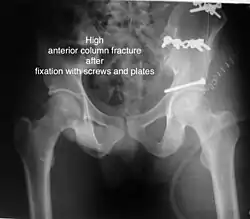

High anterior column fracture 3 D CT scan picture -

High anterior column fracture after fixation with screws and plates